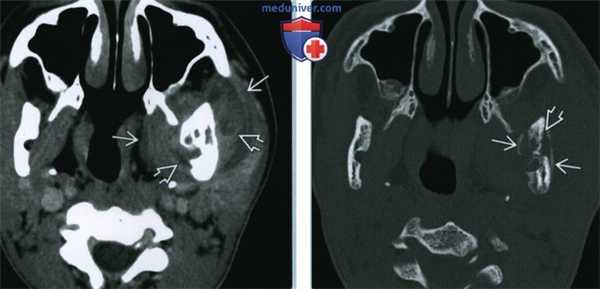

(Слева) При аксиальной КТ с контрастным усилением у девочки 15 лет, которой ранее было выполнено оперативное вмешательство по поводу перелома нижней челюсти, а сейчас возник отек левой щеки, и появилась боль, определяются выраженные воспалительные изменения в жевательном пространстве слева. Гиподенсные очаги представляют собой участки ранней трансформации флегмоны в абсцесс.

(Справа) При аксиальной КТ в костном окне у этой же пациентки определяется периостальная реакция вдоль кортикального слоя ветви нижней челюсти, а, кроме того, остеосклероз и воспалительные изменения в центре. Эти изменения позволяют сделать вывод об остеомиелите.

• КТ с КУ:

о Воспалительные изменения мягких тканей (уплотнение жировой клетчатки, утолщение кожи, лимфаденопатия)

о Может обнаруживаться абсцесс поднижнечелюстного, подъязычного или жевательного пространства